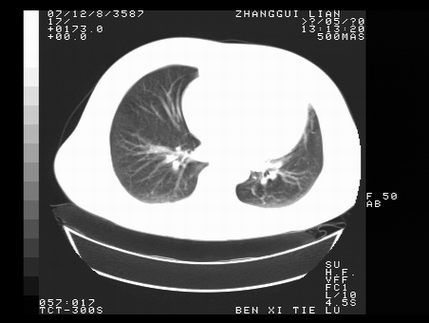

标题: CT10817:女,46,胸疼,无其他病史 [打印本页]

标题: CT10817:女,46,胸疼,无其他病史

左侧上纵隔旁团块影,部分植入纵隔,与纵隔界限不清,另:左肺门明显见团块,气管隆突前方见肿大淋巴结。考虑:左上肺纵隔型肺癌伴左肺门及纵隔淋巴结转移!

首先考虑左侧中央型肺癌伴阻塞性肺炎、纵隔内、弓旁淋巴结转移可能性大(纵隔窗调的欠佳)

1左上肺中心型肺癌伴左肺上叶不张2主动脉弓旁淋巴结转移3左下肺炎症

1 左侧中央型肺癌伴阻塞性肺炎 2 左肺门及纵隔淋巴结转移!3两侧胸腔及心包积液.

左侧胸廓塌陷,纵隔向左侧移位,左上肺不张。